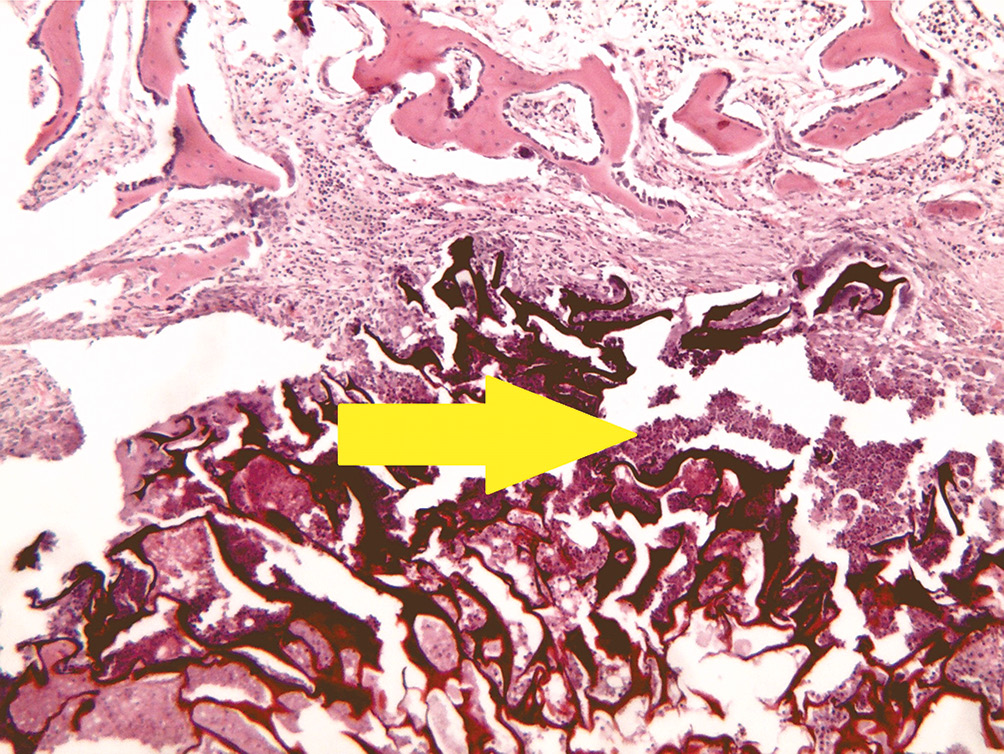

- Группа отрицательного контроля с перфорационными отверстиями (рис. 2).

Рис. 2. Группа контроля: некротический детрит с густой инфильтрацией нейтрофильными лейкоцитами и прилегающими костными балками и надкостницей. Окраска гематоксилином и эозином, увеличение ×40

В зоне дефекта костной ткани находится большое количество некротического детрита с множественными густо лежащими нейтрофильными лейкоцитами. К зоне дефекта и окружающей костной ткани прилежат надкостница и небольшие фрагменты поперечно-полосатой мышечной ткани с очаговой лимфогистиоцитарной инфильтрацией и единичными в поле зрения гигантскими многоядерными клетками типа инородных тел.